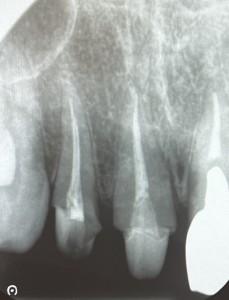

診察をしたところ、右上の差し歯は被せ物と一緒に歯が折れていましたが、幸いにも、歯根が割れていないことがわかりました。外れた差し歯の隣もすでに神経がなく、灰色に変色していました。患者様は、これを機に、右上2本を被せなおしたいとのご希望でした。

2日目〜5日目 右上1番の根管治療を行い、土台を立てました。

6日目〜7日目 右上2番の根管治療を行い、土台を立てました。